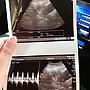

[懷孕] 照到心跳了!

[ BabyMother ]52 留言, 推噓總分: +40

作者: mythpandora - 發表於 2016/12/14 08:18(9年前)

46Fgitenmax: 恭喜恭喜12/14 14:31